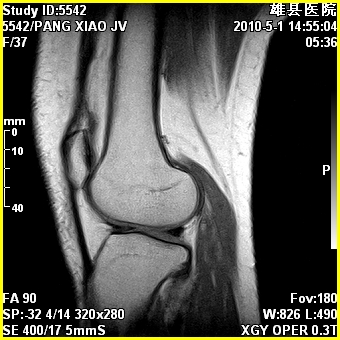

标题: MRI2894:患者右膝关节疼痛两月余,无明显外伤史 [打印本页]

标题: MRI2894:患者右膝关节疼痛两月余,无明显外伤史

右股骨下端前内侧类圆形异常信号,位于干骺端,呈长t1长t2改变,但信号不均,t1图上病灶中心见小片状稍高信号影,t2图上见散在稍低信号影,stir像呈高信号,因病灶较小,缺乏特征性改变,结合患者年龄及部位,考虑嗜酸性肉芽肿可能性大。胫骨关节面下的小囊状异常信号,如果一元论考虑则为嗜酸性肉芽肿,不过发生在这个部位的少见,二元论考虑为邻关节骨囊肿。半月板与前后交叉韧带均未见异常。

右股骨下端前内侧干骺端囊性良性病变,考虑 1内生软骨瘤 2骨囊肿 3肉芽肿。